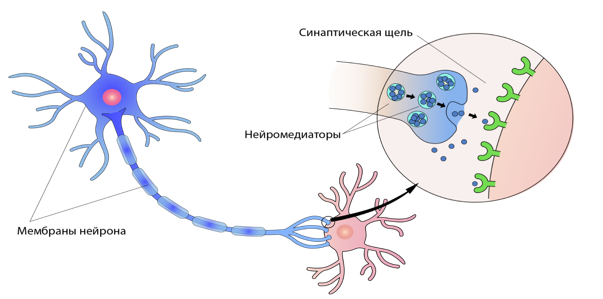

Работает принцип передачи сигнала (возбуждение/торможение), а также структурный иерархический принцип (стимул – реакция).

Человеческий головной мозг — командный центр нервной системы, образован из клеток – нейронов. Нейроны мозга способны формировать новые связи и адаптироваться под воздействием окружающей среды — это называется нейропластичностью. Головной мозг

Поверхность коры за счет борозд и извилин увеличивается и равна ~ 220 тысячам квадратных мм. Между оболочками М и П – спинномозговая жидкость (цистерны); между П и Т – серозная жидкость. Сигналы от разных органов чувств поступают в мозг с разной скоростью, чтобы потом мозг создал из них единую картину. Нервные импульсы перемещаются по расположенным в мозге нейронам со скоростью около 440 километров в час. Мозг состоит из около 86 миллиардов нейронов, которые обрабатывают информацию и передают сигналы. Мозг вырабатывает в течение дня около 70 000 мыслей.

Мозг не может существовать ни без кислорода, ни без глюкозы. Головной мозг потребляет для питания 50 % глюкозы, вырабатываемой печенью и поступающей в кровь. В нашем мозге находится около 86-100 млрд нейронов. Нейронов в коре ~15 млрд и у каждого от 7 до 10 тыс. связей с соседними клетками. Нейроны в мозге человека питаются благодаря глиальным клеткам, которых у нас примерно по триллиону на каждого. Клетки мозга не делятся, и погибшие не восстанавливаются. Осложнения даже после простого гриппа могут быть губительными.

Пациент заметил, что у него онемел мизинец на руке. Он думал – мелочь. Но оказалось, что это начало серьезной болезни – рассеянного склероза. Исчезает миелин – изоляция вокруг нерва. Нерв, теряя изоляцию, выходит из строя, сигналы через него перестают проходить. Организм перестает подчиняться сигналам мозга, становится неподвижным и медленно умирает. От этого заболевания умер Николай Островский, свою книгу “Как закалялась сталь” он сумел лишь продиктовать.